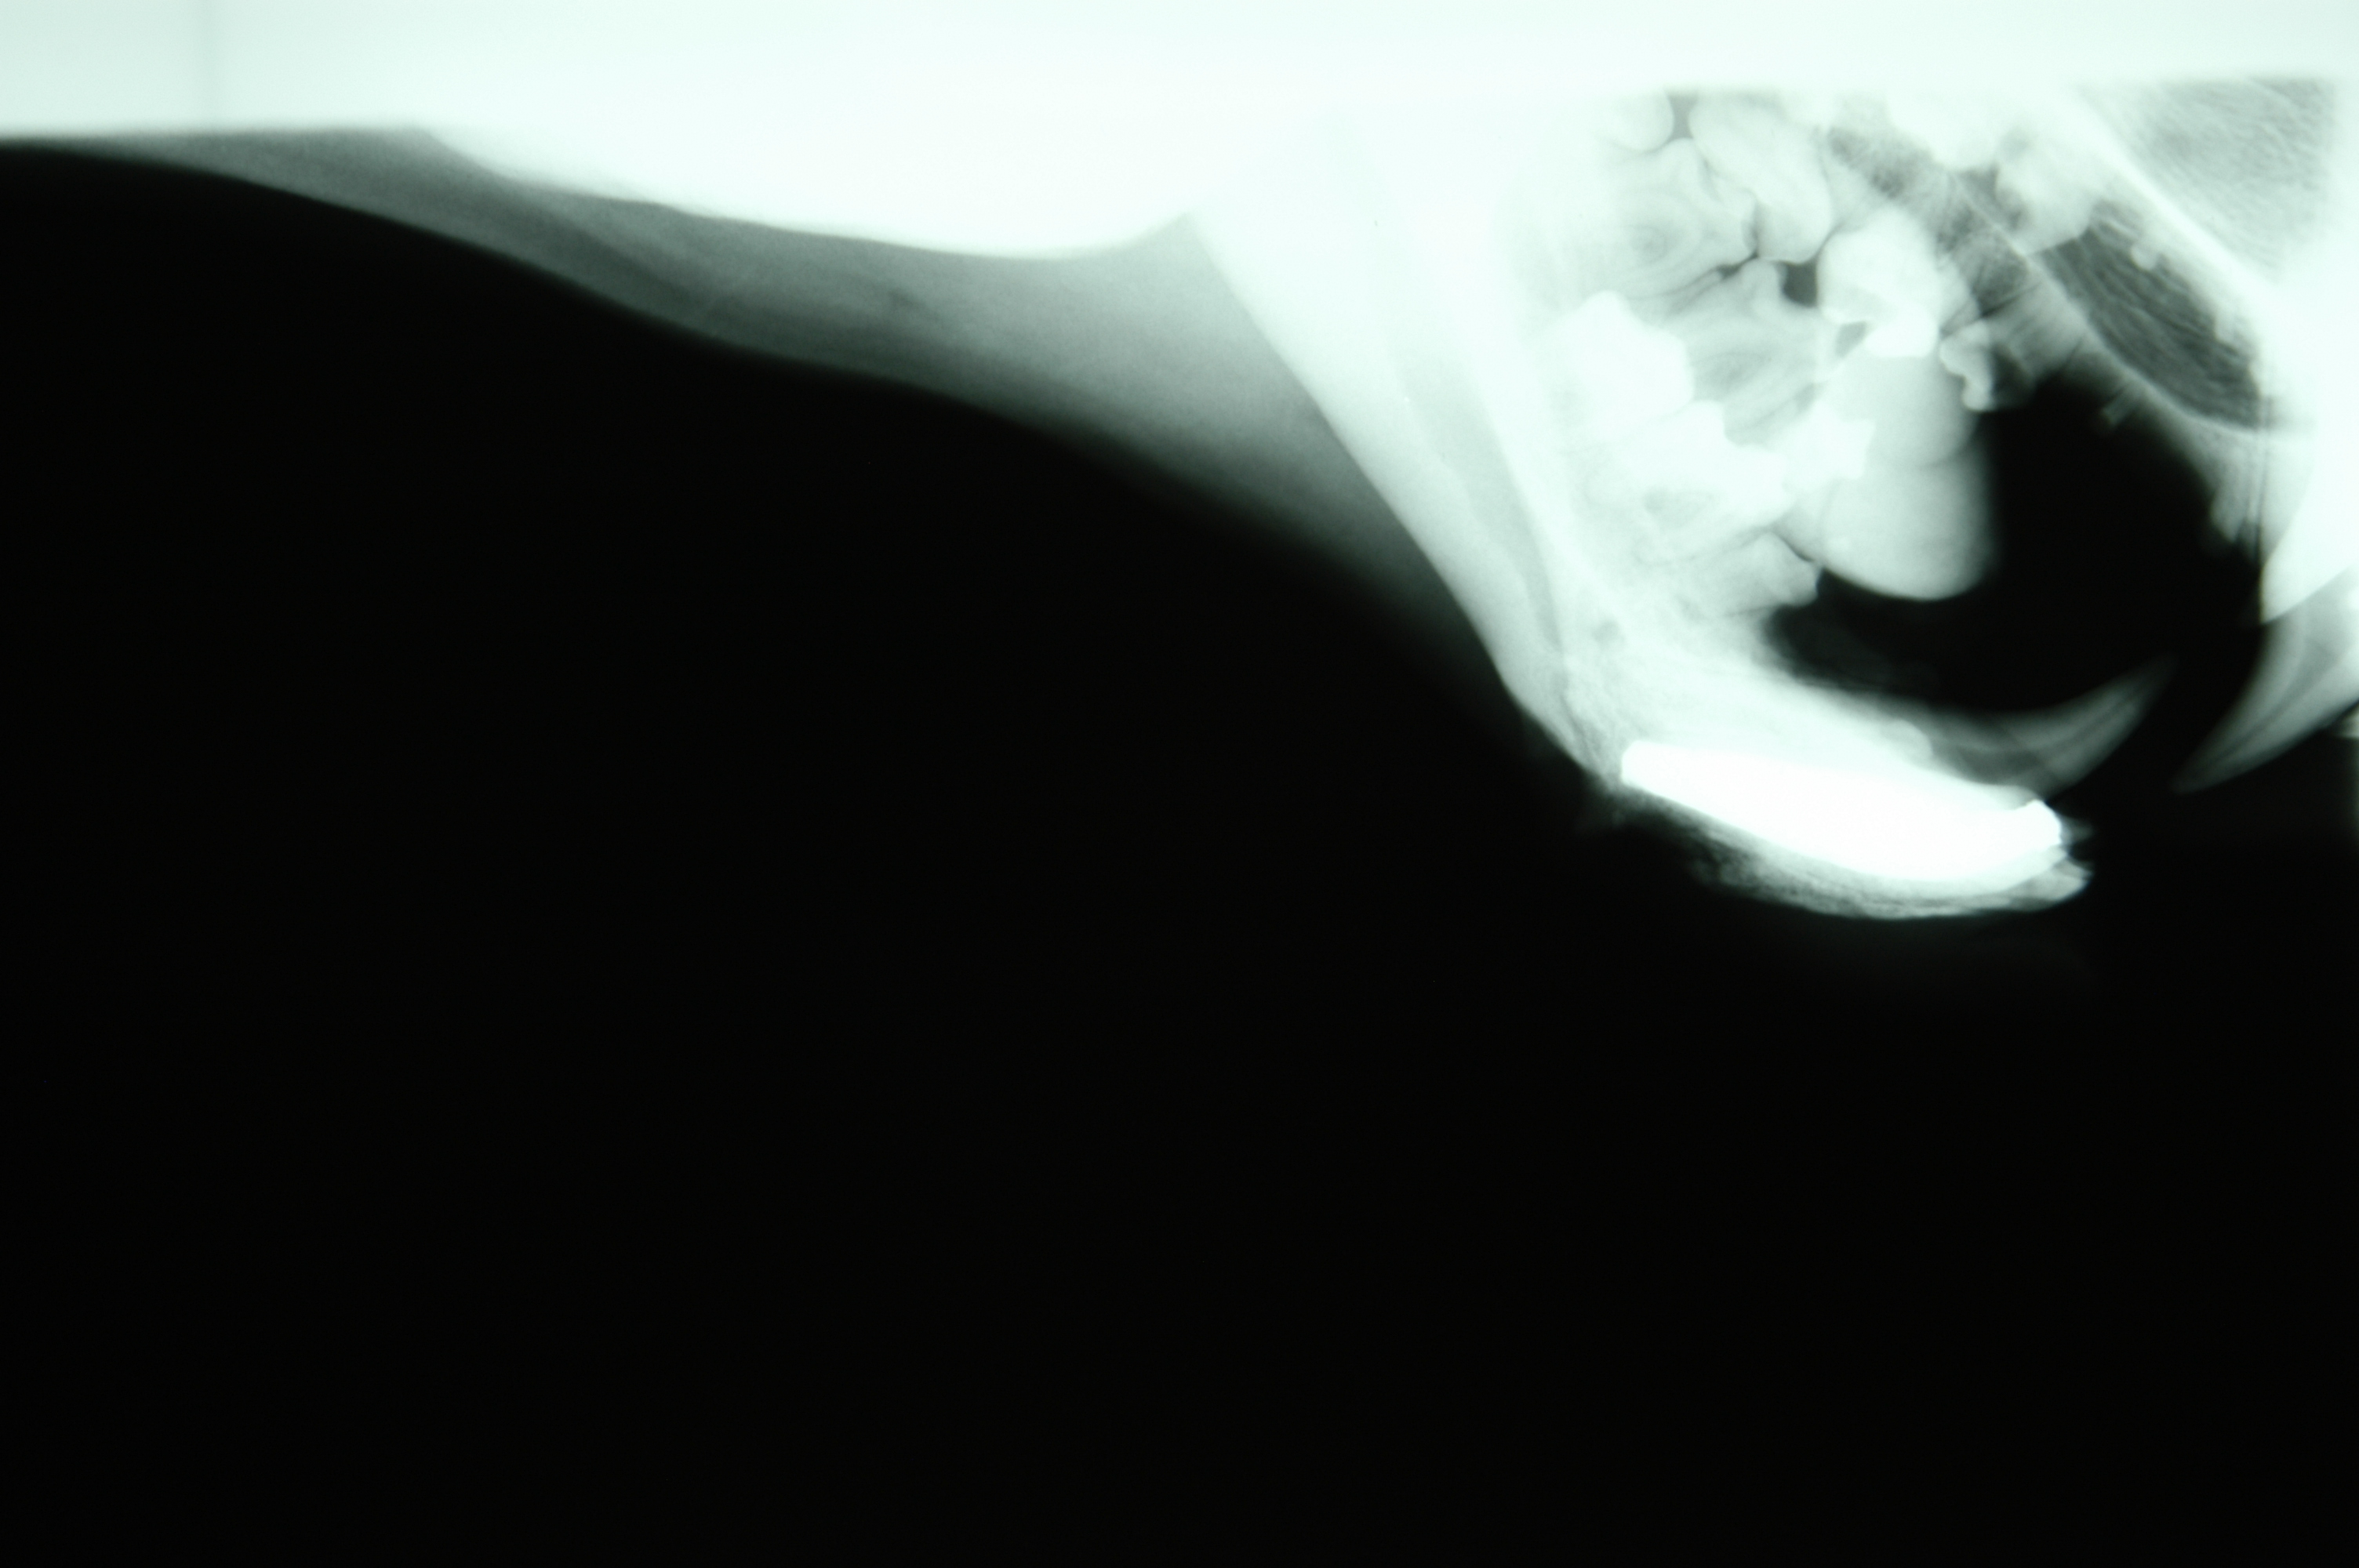

Bongo “Ira” mandible symphysis fracture presentation.

July, 1987Milwaukee County Zoo.Bongo female, “Ira” fractured her mandible through the cartilaginous symphysis when she panicked and ran into an enclosure wall. She had done this before, fracturing her mandibular incisors, which had been observed by her keepers. However, she had not been sedated for an exam by the veterinarians, in great part because of her skittish nature.

When she was anesthetized the night of this severe injury, July 4, 1987, it was apparent that the anterior segment of her mandible was infected because of the multiple fractured incisors and the infected bone had become severely weakened. Fortunately, the posterior segment of the cartilaginous symphisis was intact and still held the right and left mandible bodies connected. Zoo veterinarian, Dr. Bruce Beehler anesthetized “Ira” and we examined the fracture. With the help of a large animal veterinarian I used ligature wire to lift up the anterior segment, securing it to the still intact mandible symphisis. We understood that this was just a temporary fix. Soon after “Ira” was awake she began to feed and put downward pressure on the repair.

I enlisted the aid of veterinary surgeon Dr. Paul Howard from the University of Wisconsin School of Veterinary Medicine. He came to Milwaukee County Zoo the next evening, July 5, with a surgical assistant and appropriate orthopedic equipment. After removing the ligature wire repair and debriding the wound he reduced the fracture securing it with six intermedullary pins. Extensive suturing was necessary to repair the damaged tissues. The pins held the reduction.

Over time some of the pins loosened and came out. However, the reduction held and the mandible healed in place with modest malposition and a slightly drooping lip. “Ira” lived for several years and had healthy calves.